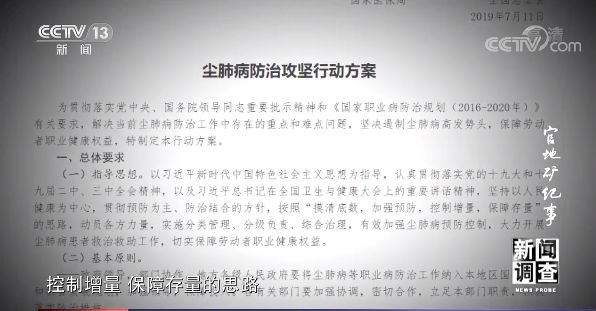

2019年,国家卫生健康委等10部门联合制定《尘肺病防治攻坚行动方案》,按照“摸清底数,加强预防,控制增量,保障存量”的思路,加强尘肺病预防控制,开展尘肺病患者救治救助工作。